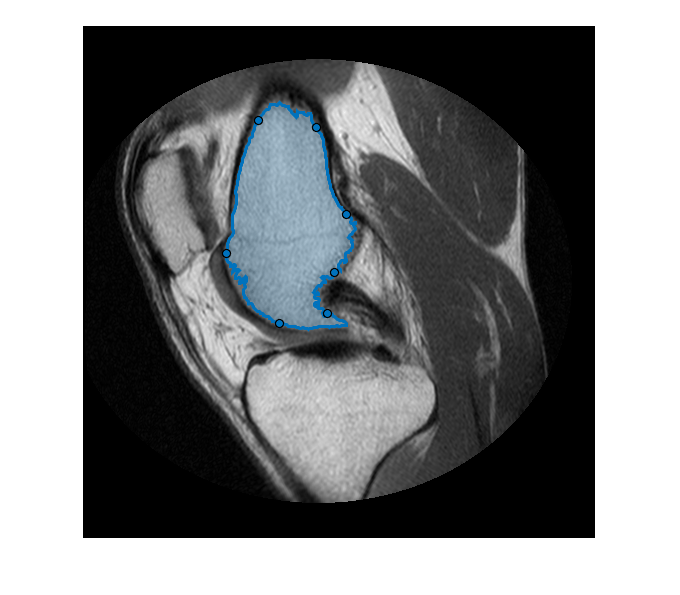

Create a Freehand ROI that follows the shape of a segmentation mask. For more details on this process, see Use Freehand ROIs to Refine Segmentation Masks.

Read MRI data into the workspace.

im = dicomread('knee1.dcm');

Segment the MRI image and select the two largest regions of the mask.

segmentedLabels = imsegkmeans(im,3); boneMask = segmentedLabels==2; boneMask = bwareafilt(boneMask, 1);

Create a freehand ROI inside the segmented mask.

hf = drawfreehand('Position', pos);